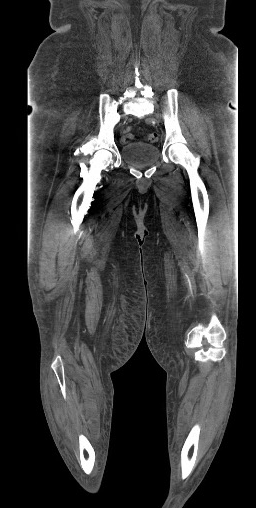

A 37 yo M w/ a PMH of type 2 DM and non-ischemic cardiomyopathy presents to the ED with 6 days of progressively worsening L lower extremity pain. On exam, the L lower leg is slightly erythematous/edematous and is cool to touch when compared to the R. There is decreased sensation in the L foot. On Doppler exam, the L PT pulse is normal, but DP pulse is weak. A CTA runoff is obtained. What's the diagnosis? (scroll down for answer)

Answer: Occlusion of the L superficial femoral artery